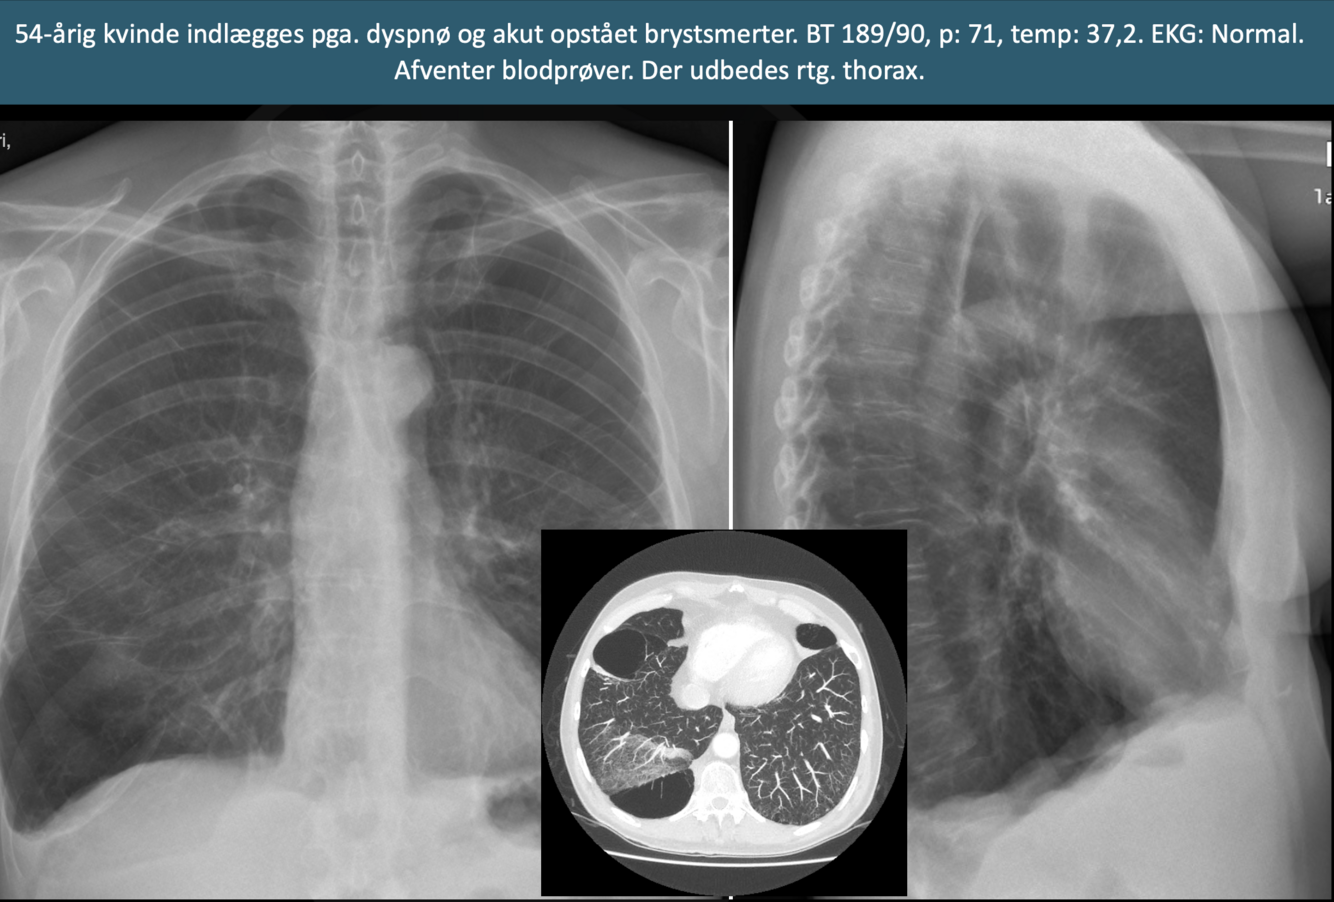

Q

Diagnose?

A

Højresidig pneumothorax